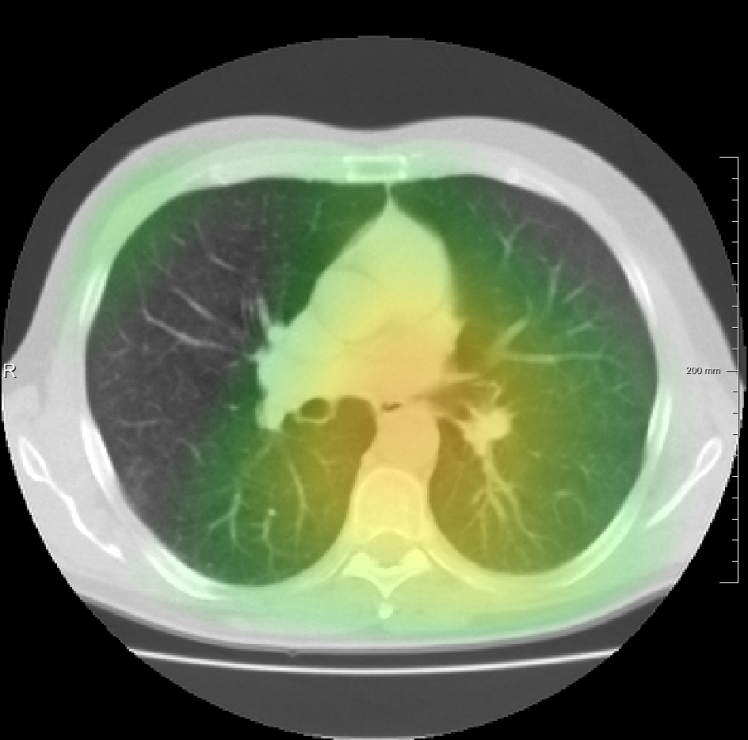

In total we generate 14 basis types of artificial DVFs: 5 single frequency, 4 mixed frequency, 4 respiratory motion and 1 identity. The precise settings of the parameters are available in Table I and examples are given in Fig. 4. The histograms of the Jacobians are also available in this figure. When the spatial frequency is increased, the Jacobian histograms will spread more, which shows that local relative volume changes are increased. The value of , the maximum artificial displacement along each axis, is chosen as 20, 15 and 7 for RegNet4, RegNet2 and RegNet1, respectively.